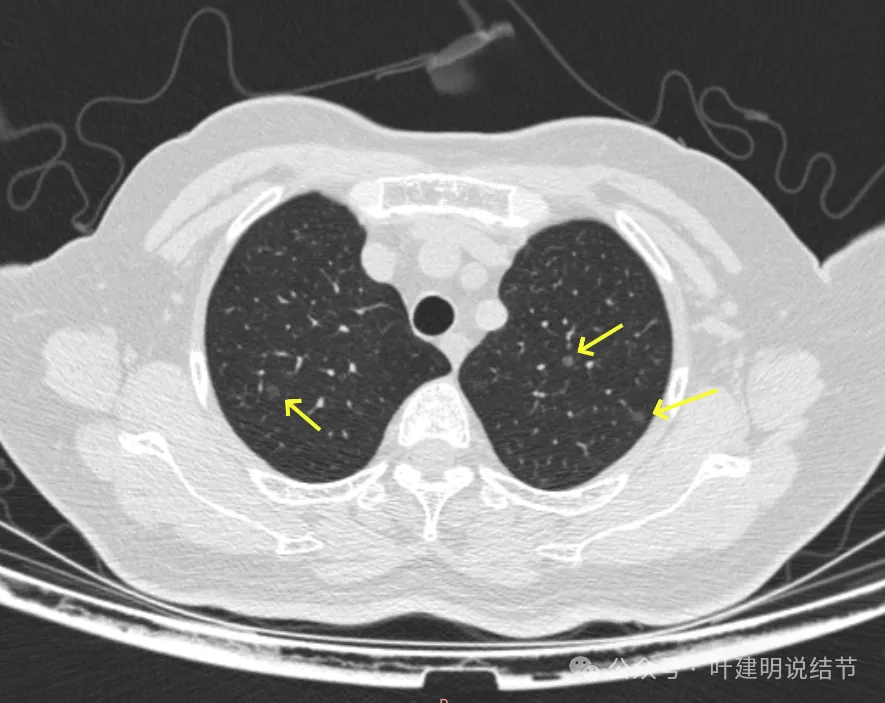

病灶23-26:两肺微小淡磨玻璃结节,轮廓较清。

病灶27-30:两肺微小淡磨玻璃结节,轮廓较清。